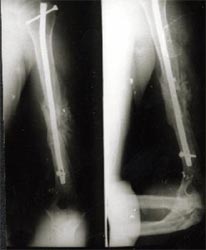

病例三、

肱骨骨不连的骨断端多有硬化而骨干骨质疏松、遗留有以往手术钢丝、

钉孔,骨吸收骨干变细皮质变薄,有严重骨缺损。

带锁髓内钉在骨组织和钉体之间提供较均匀的弹性应力分布,避免钢板内固定时

广泛的软组织剥离,抗旋转作用强于可屈髓内钉,不需外固定,对断端稳定性好